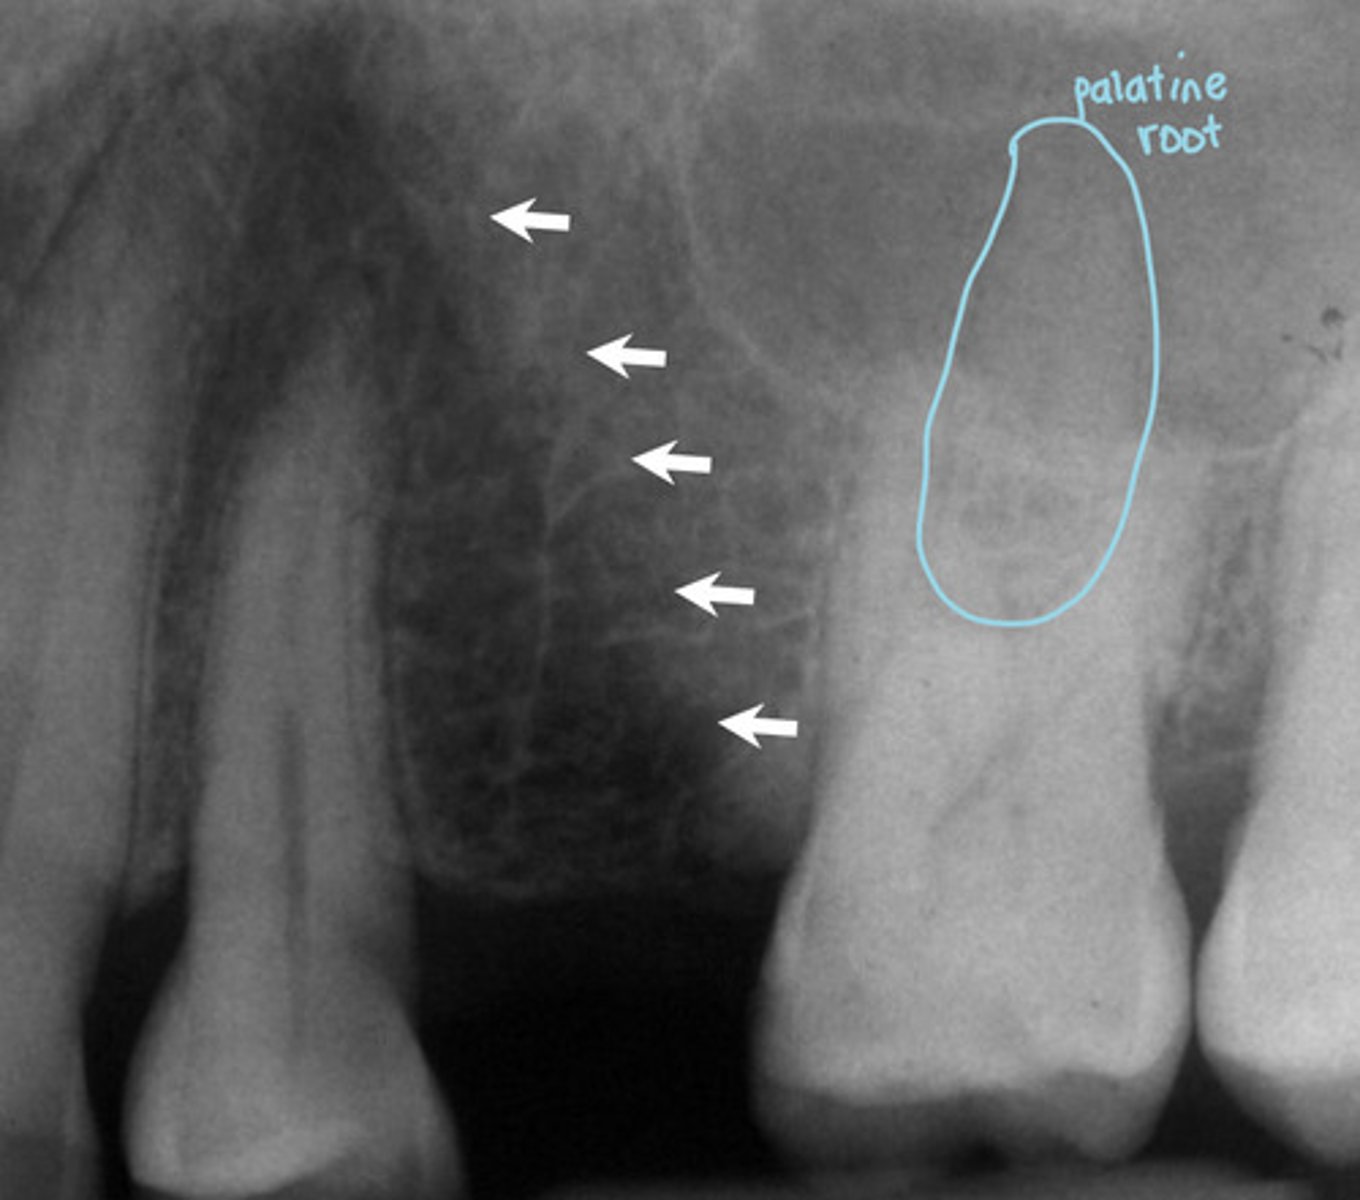

What are the white arrows pointing to?

Lateral fossa